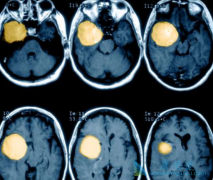

绝大多数脑膜瘤患者可通过手术、放疗或两者联合治疗获得满意的疗效。但仍然有不少患者脑膜瘤复发,这类脑膜瘤称之为手术和放疗难治性脑膜瘤(以下称为难治性脑膜瘤)。针对此病一直以来没有理想的药物可供选择。 索坦 (sunitinib)是一种口服的酪氨酸激 ...